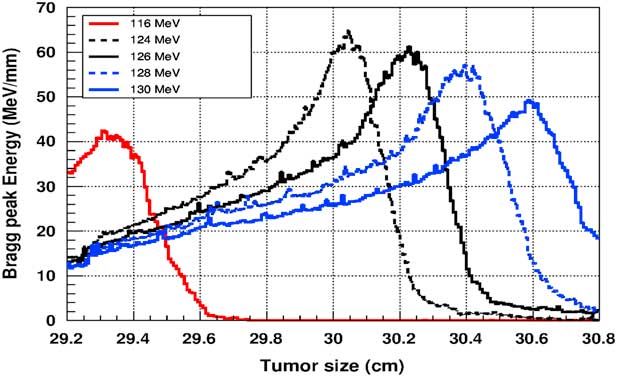

Figure 5 shows the plot of the deposited energy of a monoenergetic proton beam along the tumour size. As this figure shows, to surround completely a such tumour we should use a proton beam energy, ranging between 116 and 126 MeV. For this range energy, the Bragg peak energy is around 40 MeV and the half-value width for each Bragg peak is about 50% of the tumour size. The effect of adding gold in the tumour on the Bragg peak energy is shown in Figure 6. In this figure, we notice that the Bragg peak is localised in the tumour for the proton beam energy ranging between 116 and 130 MeV. The Bragg peak energy at the centre of the tumour is greater than without GNPs, in this case, with the presence of GNPs, the proton therapy is enhanced up to 75%, this is due to the concentration of GNPs at the centre of the tumour. Moreover, for high proton beam energy like 130 MeV, the width at half height of the Bragg peak is around of 75% of the tumour size. Comparing with previous results, the presence of GNPs in the tumour makes the width at half height of Bragg peak larger. This result shows that adding GNPs in tumours makes the proton therapy easier in clinical medicine and presents more benefit. Similarly in Figure 7, we plotted the deposited energy in the tumour with the presence of nanoplatinum materials. In this figure, the Bragg peak is localised in the tumour for the proton beam energy ranging between 116 and 132 MeV. Comparing with previous results, the width at half height of the Bragg peak is spread over 85% of the tumour. Moreover, the deposited energy at the centre in the tumour is almost double comparing with the same results in Figure 6. In the case of the use of silver NPs during this therapy, the plot of the deposited energy has the same shape as in the case of the use of GNPs (see Figure 8).

Figure 5 The deposited energy of a monoenergetic proton beam into a spherical tumour with a diameter of 1·5 cm. Notes: The proton beam energy is ranging between 116 and 126 MeV.

Figure 6 The deposited energy of a monoenergetic proton beam into the tumour with adding gold nanoparticles. Notes: The proton beam energy is ranging between 116 and 130 MeV.

Figure 7 The deposited energy of a monoenergetic proton beam into the tumour with adding platinum nanoparticles. Notes: The proton beam energy is ranging between 116 and 132 MeV.

Figure 8 The deposited energy of a monoenergetic proton beam into the tumour with adding silver nanoparticles. Notes: The proton beam energy is ranging between 116 and 130 MeV.